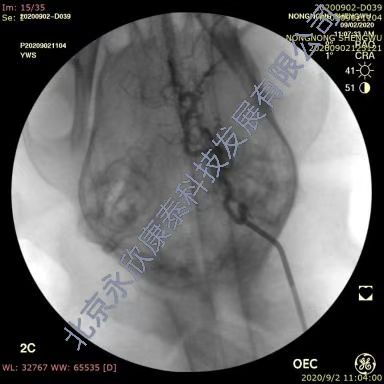

采用介入手术建立比格犬急性血栓性脑血管闭塞动物模型,分别于两侧腹股沟区备皮,消毒铺巾,穿刺右股动脉置入导管鞘,置入导丝,将5F单弯导管插至颈内动脉近端手推注显影剂确定血管走向,正侧位造影判断血管走行情况。用1mL注射器吸3~5条血栓条注入颈内动脉,造影证实颈内动脉颅内段末端栓塞,2h后造影复查血管的灌注情况,证实栓塞血管没有因血栓自溶复通,之后30min匀速脉滴注阿替普酶。溶栓治疗后1h,脑血管造影,判断血管复通情况,进行评分。